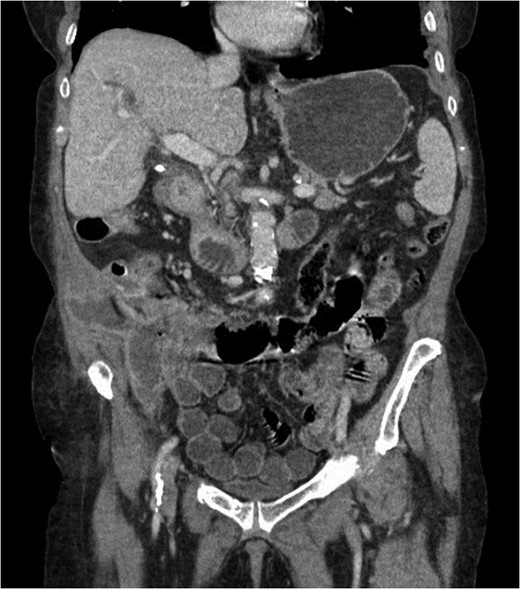

At presentation her vital signs were stable. Abdominal exam revealed exquisite tenderness in the right lower quadrant, with no evidence of digital clubbing. Blood-work revealed an elevated WBC of 15.6. A CT scan demonstrated a 4.3 cm annular mass within the cecum, suspicious for a primary colonic malignancy, as well as an 8.6 × 8.2 cm2 lobulated gas-containing abscess with extension in to the lateral abdominal wall (Figs 4 and 5).

Abdominal CT scan showing annular cecal mass with evidence of perforation.